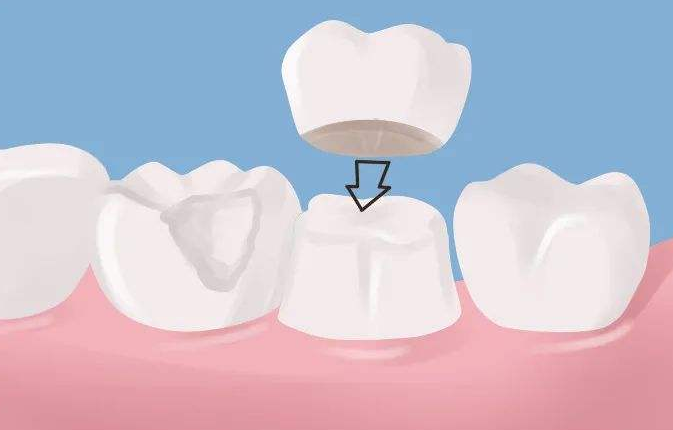

為什麼根管治療後需要帶牙冠?

根管治療後,醫生也會建議你戴牙冠,但很多人不理解。根管治療後牙齒不疼,補一補就可以了。為什麼需要做牙冠保護?覺得沒必要。事實上根管治療後,沒有牙髓營養的牙齒會變脆,剩餘的牙冠容易斷裂和開裂,導致牙齒使用壽命降低。因此根管治療後,需要一個牙冠來保護治療後的牙齒。